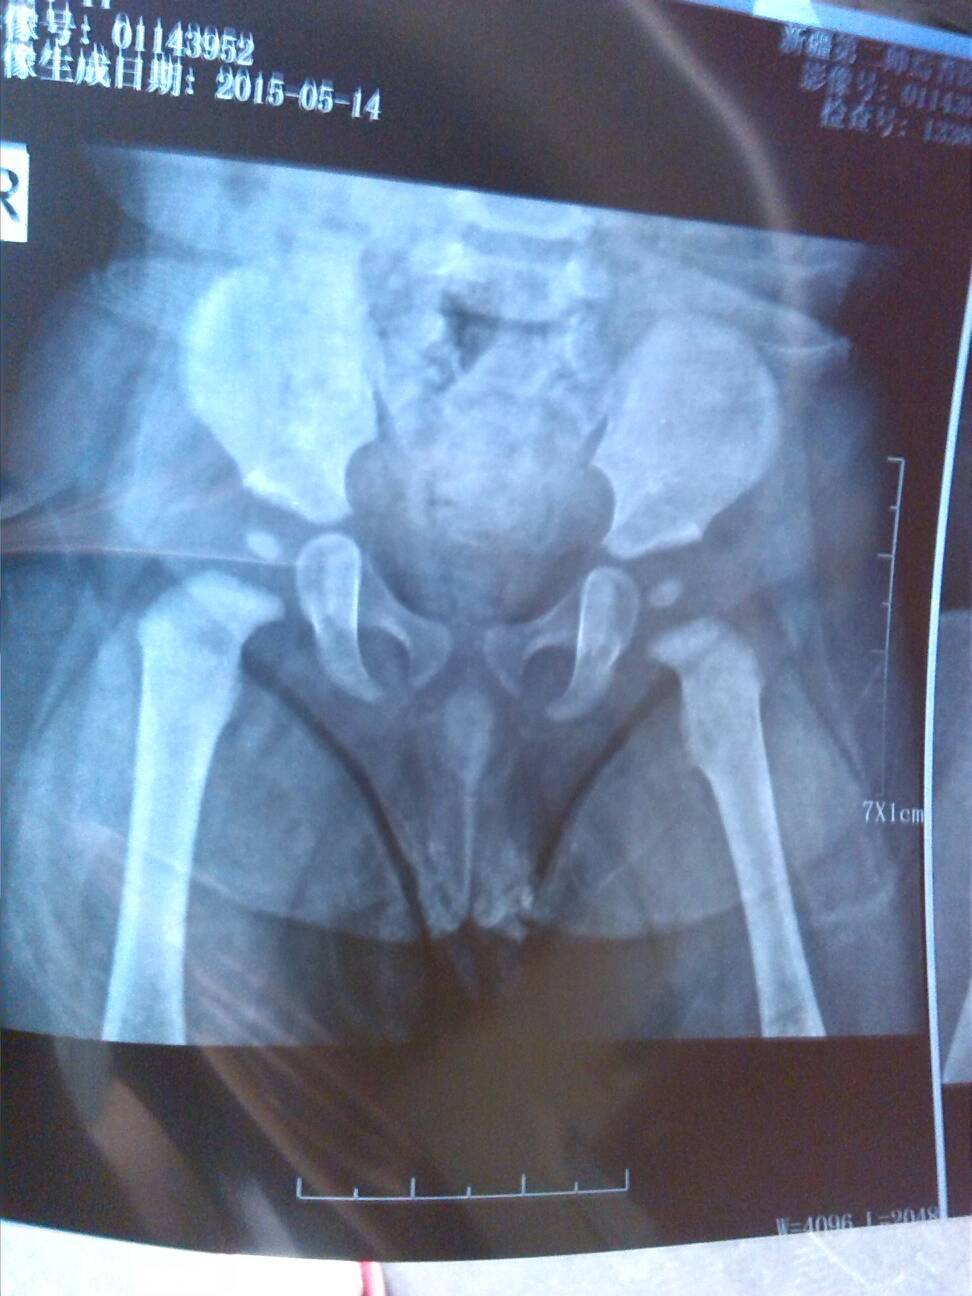

宝宝半岁,两个脚一大一小,腿纹也对不齐,脚后跟也对不齐,脚小的腿还可以听到骨头响,今天去拍了片 点击展开 匿名用户 2015-05-14 16:51 推荐回答 看旧旧看医生是怎样评估,需要怎样的治疗,另外适当给孩子补充营养,瓣以峡是可悟坐以改善的 WQ1093523039 2015-05-16 11:24 宝宝知道提示您:回答为网友贡献,仅供参考。 为您推荐: 其他回答 去医院好好查查,小孩还小看有没有后天来弥补 匿名用户 2015-05-14 17:30 相关问题 医生你好,为什么出月子十天了还能累着脚,今天走了一小段路脚后跟又累着了,骨头很疼,请问什么原因请问 宝宝刚出生没多久 膝盖下腿弯处长了个脓包 吃了消炎药脓包挤了以后 宝宝的脚后跟就不敢沾地了 坐月子今天四十二天了出去转了一圈会来腿疼屁股疼要疼脚后跟疼会不会留下什么病